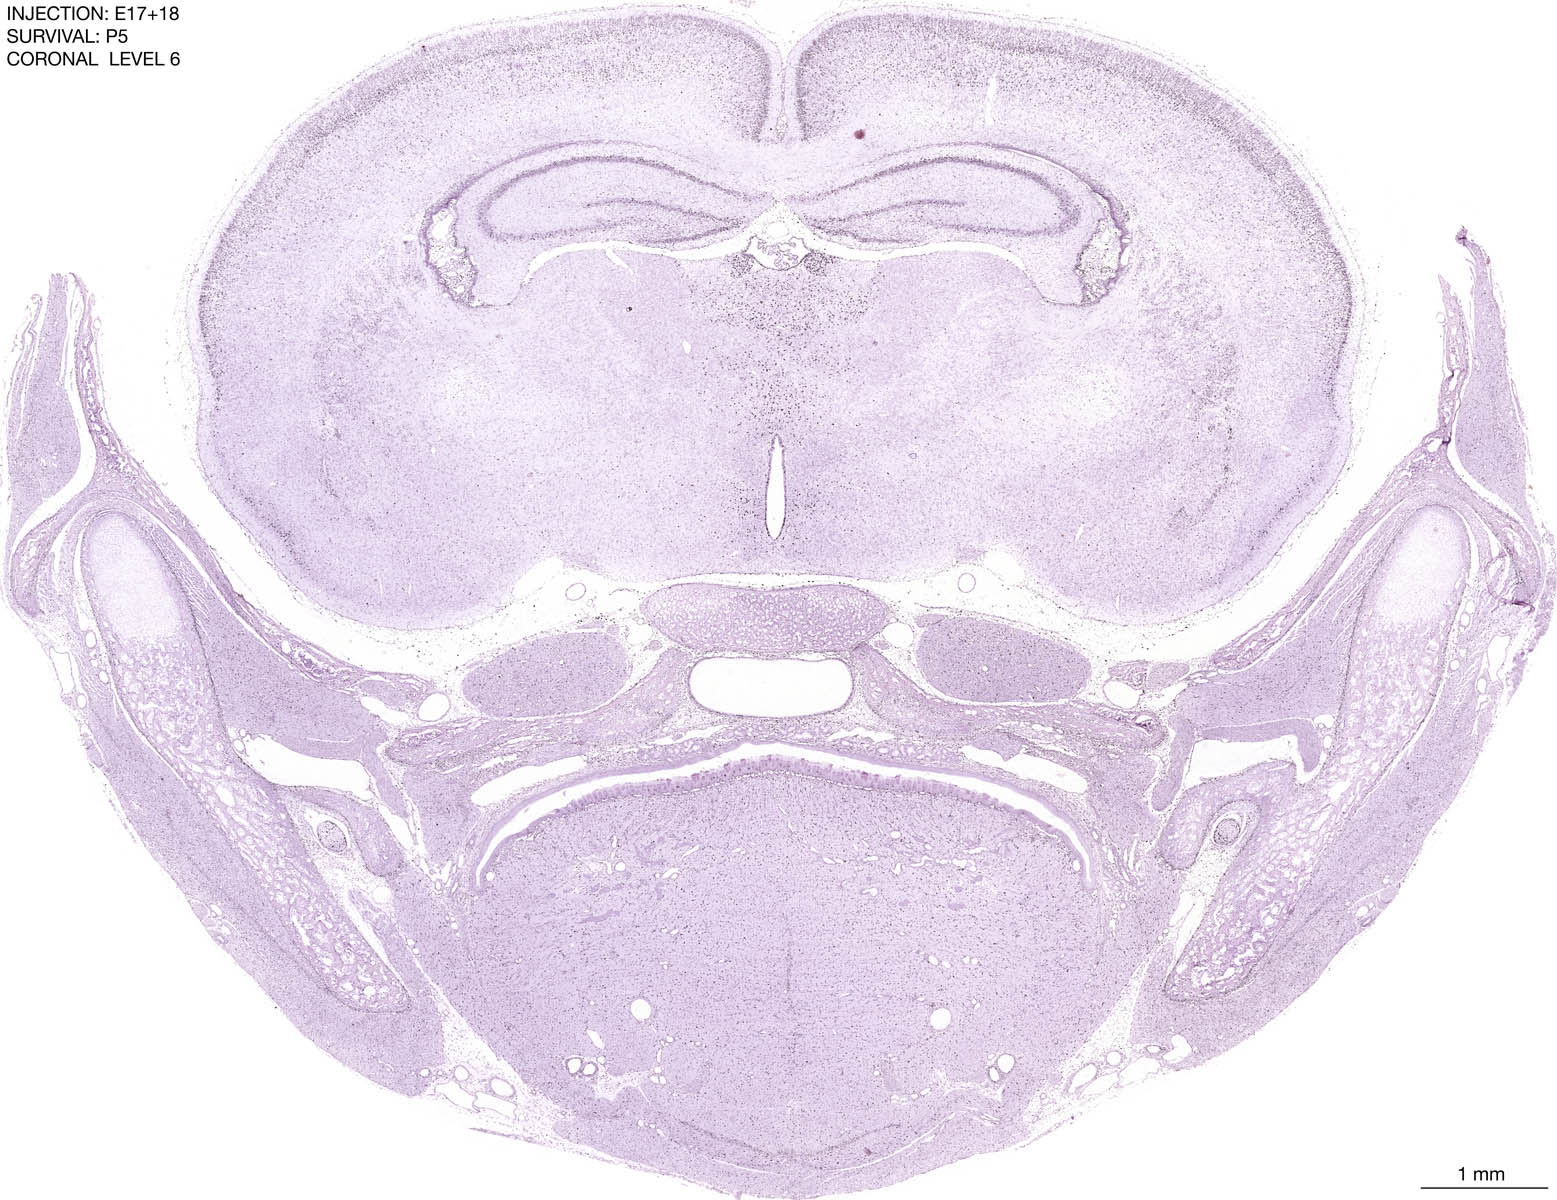

E17+18 P5 Survival The images below are from the brain of a rat that was exposed to tritiated thymidine on E17+18 and survived to P5. Download: Large | High Res Download: Large | High Res Download: Large | High Res Download: Large | High Res Download: Large | High Res Download: Large | High Res Download: Large | High Res Download: Large | High Res Download: Large | High Res Download: Large | High Res Download: Large | High Res Download: Large | High Res Download: Large | High Res Download: Large | High Res Download: Large | High Res Download: Large | High Res Download: Large | High Res Download: Large | High Res Download: Large | High Res Download: Large | High Res Download: Large | High Res Download: Large | High Res Download: Large | High Res Download: Large | High Res Download: Large | High Res Download: Large | High Res